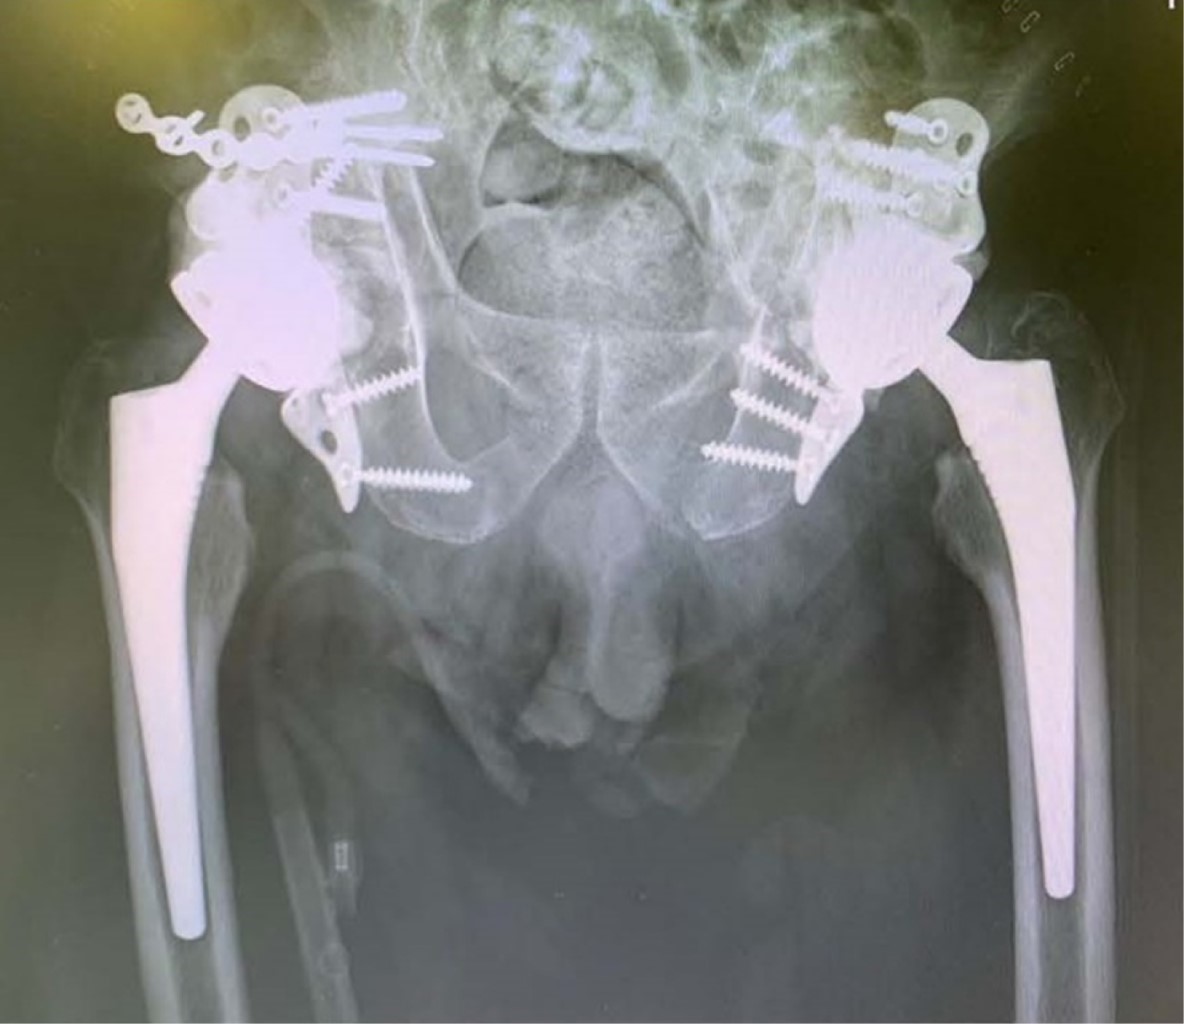

Clínicamente, el paciente presentaba un acortamiento de la extremidad inferior derecha en comparación con la contralateral, rotación externa y bloqueo articular a la realización del log roll test en ambas extremidades. Presentó impotencia funcional de ambas caderas. Dado el estado del paciente a su llegada a urgencias, no fue posible valorar el estado neurológico. No presentaba signos de heridas externas ni hematomas. Pulsos distales presentes a nivel pedio. Movilizaba extremidades superiores. Se realizó radiografía de tórax y anteroposterior de pelvis como parte del código de paciente politraumatizado, a la espera de completar estudio con tomografía computarizada (TC) abdomino-pélvico. En la radiografía de pelvis se diagnosticó luxación femoral de manera bilateral (Figura 1). Al paciente se le realizó una angiotomografía computarizada para descartar lesiones vasculares dada la inestabilidad hemodinámica que presentaba a su llegada. Se descartó lesión vascular tras la realización de la misma. En la reconstrucción 3D-TC de pelvis se objetivó fractura acetabular transversa bilateral según la clasificación de Letournel y fractura longitudinal del ala ilíaca derecha junto con protrusión intrapélvica de ambas cabezas femorales (Figura 1). Tras valoración inicial, se procedió a colocación de tracción transesquelética supracondílea femoral en ambas extremidades y retirar la cincha pélvica. El paciente estuvo ingresado en la unidad de reanimación hasta la cirugía, donde permaneció con las tracciones hasta la intervención.

Figura 1